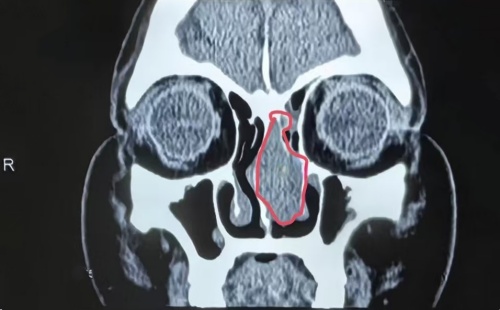

接诊李女士后,周建波主任医师立即与治疗团队分析病情,虽然肿瘤发现较早,但核磁结果显示,其累及前颅底,术中不仅要控制出血,还要修复缺损颅底,同时避免颅内并发症,患者接受手术才半个月,再次手术风险较高,但嗅神经母细胞瘤生长速度快,容易转移到其他器官,需要马上手术。

周建波主任医师介绍,嗅神经母细胞肿瘤是一种比较少见的来源于嗅区黏膜神经上皮细胞的鼻颅底肿瘤,起初症状不明显,可能有鼻塞、鼻出血、嗅觉下降等症状,与感冒、鼻窦炎的症状十分相似,发展期也具有极强的隐蔽性,大多数患者早期没有任何症状,也容易被误诊为鼻息肉,常常需要结合CT或核磁及增强扫描检查才能发现。如果遇到单侧鼻腔长肿物,建议在有条件的耳鼻喉专科进行全面的检查,以免耽误病情,延误治疗。(耳鼻喉三病区 王元元 王娟)